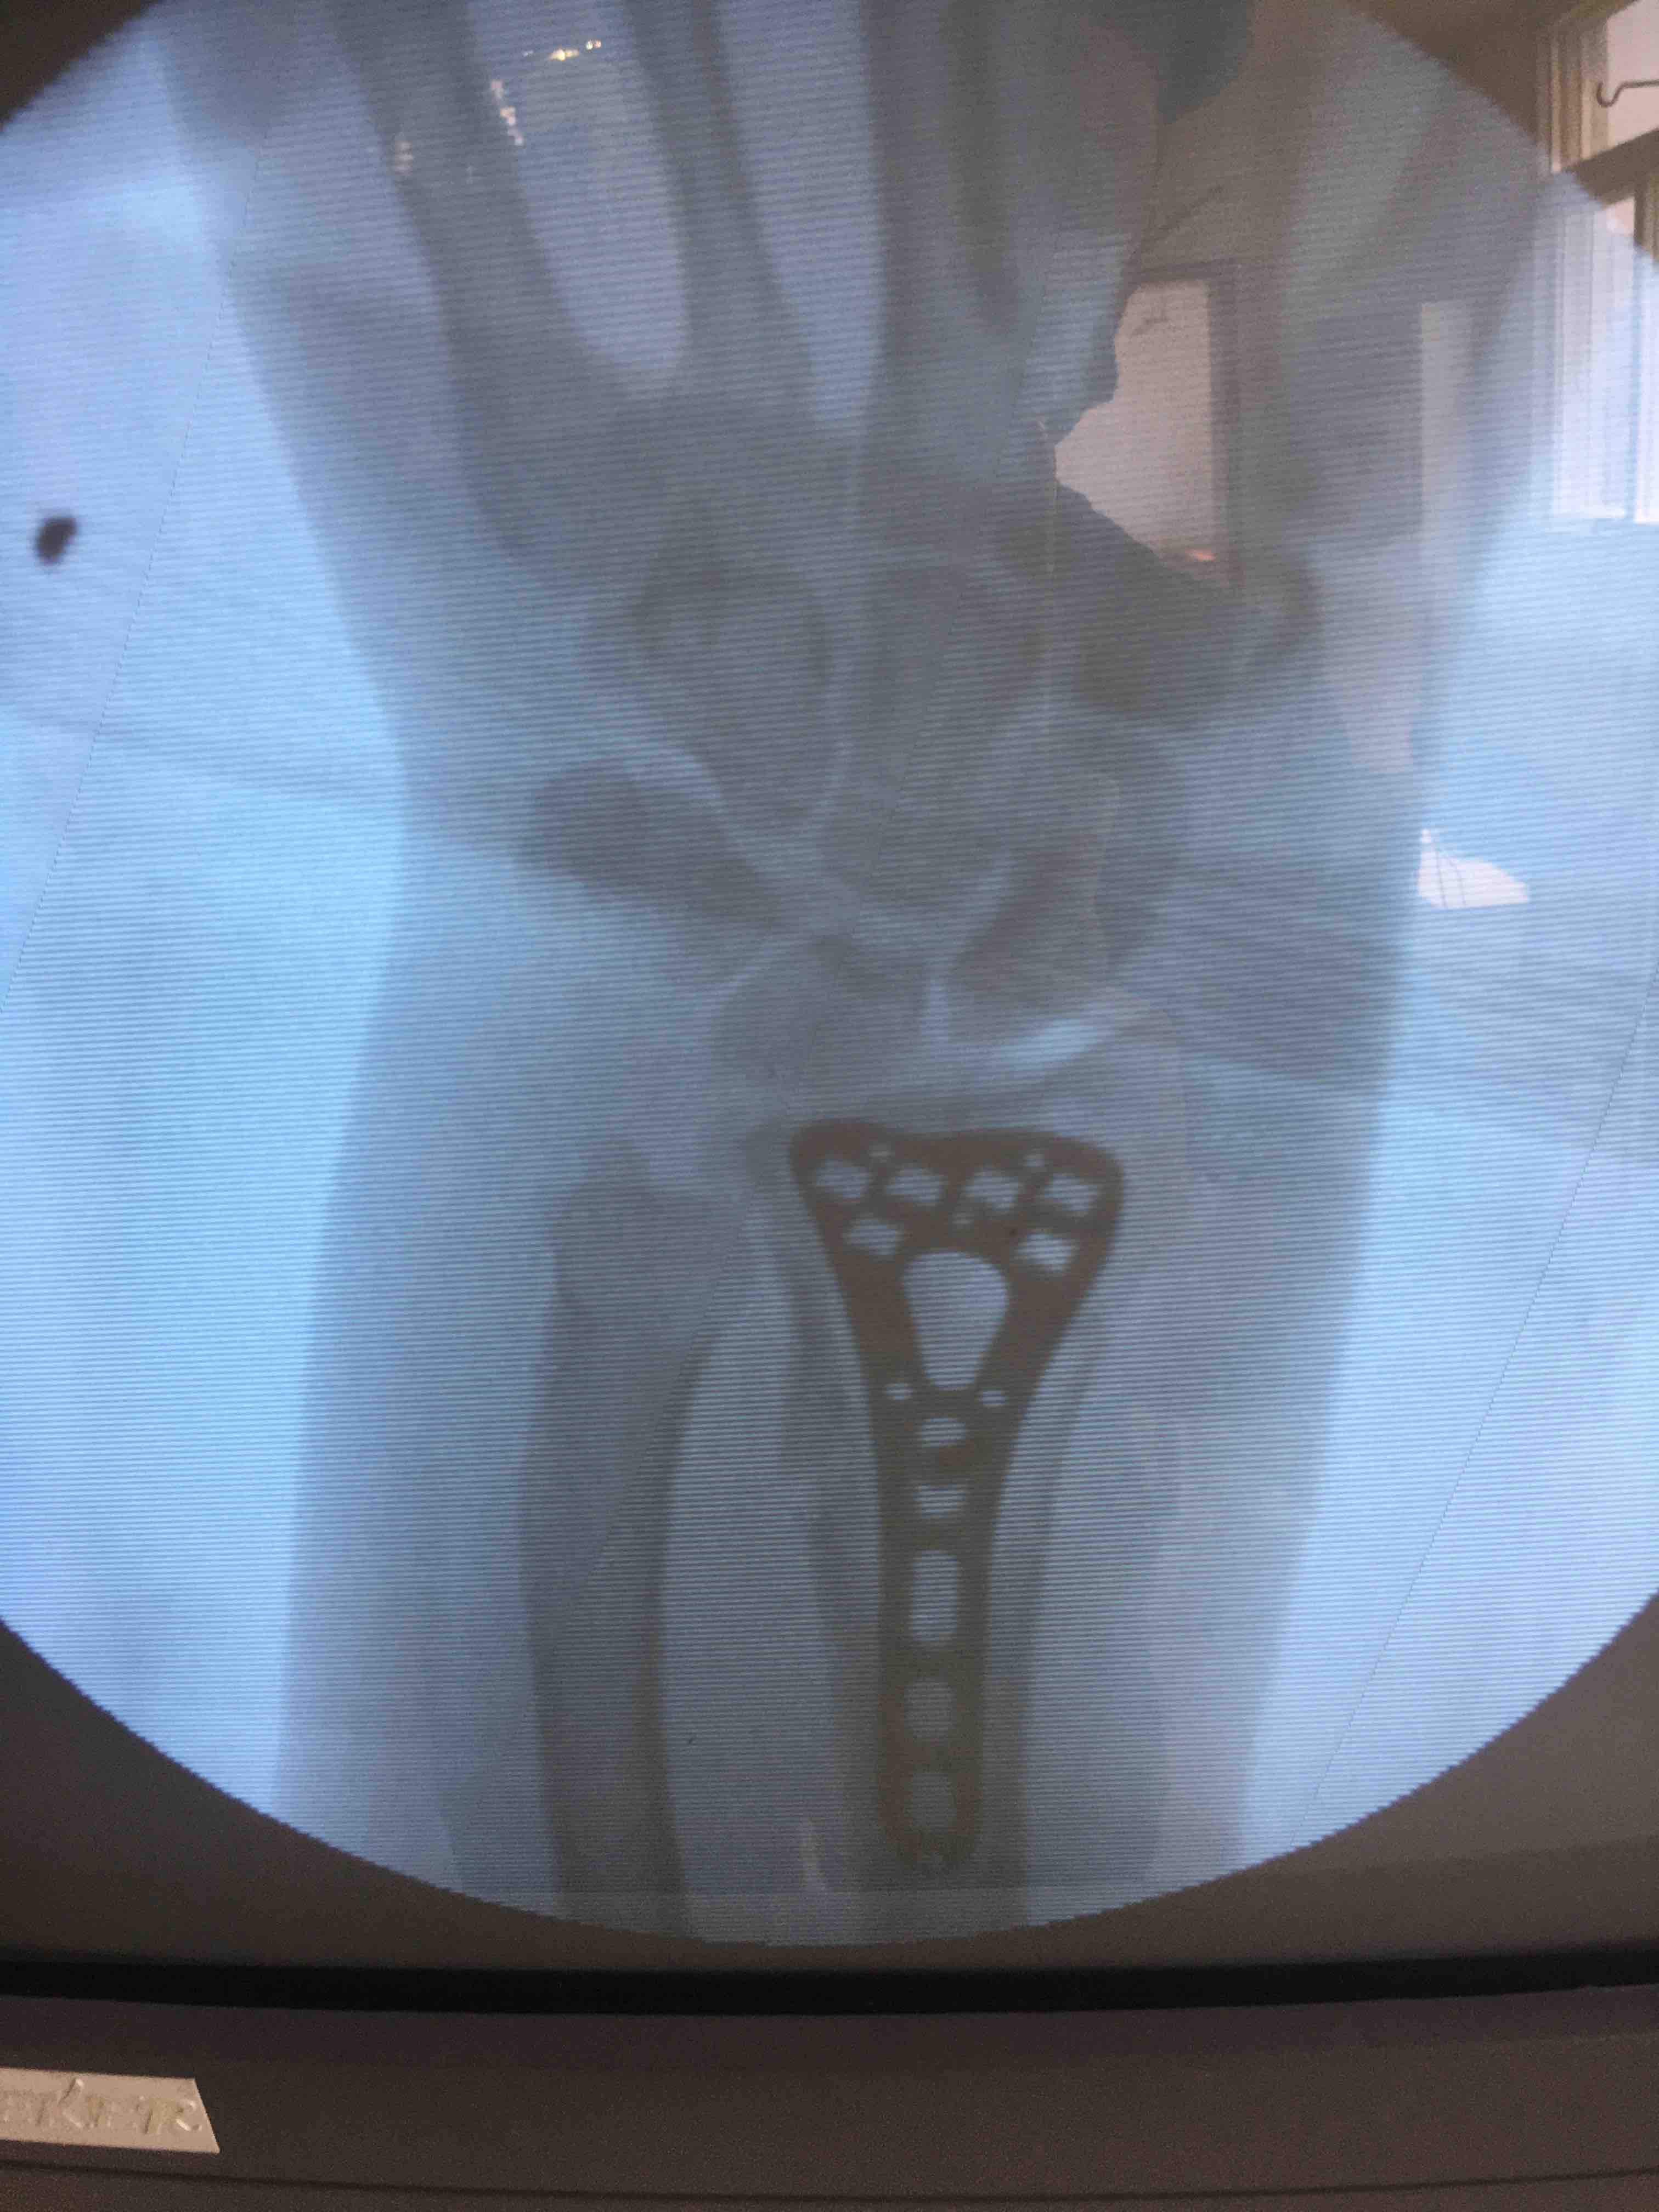

切开复位内固定术,术后抗炎,消肿等处理。